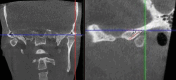

The success of complex prosthodontic treatment is believed to be conditioned by condylar path replication in the articulator, as there is a continuing debate in the scientific community regarding the anatomical relationship between joint and dental morphology. The purpose of this study was to investigate the potential correlation between incisal and condylar guidance. The study population consisted of 20-30-year-old full dentate individuals with Angle class 1 occlusion, whose cone-beam computed tomography (CBCT) scans were analyzed by two investigators. The anterior slope of the right and left glenoid fossa angle and the palatal slope of all maxillary frontal teeth were measured by software tools at three defined landmarks, and the mean values were calculated. Statistical analysis was performed using IBM SPSS Statistics software (version 19.0), and the Pearson r coefficient test was used to assess correlations. The results reveal a highly statistically significant correlation between median condylar slopes and between median incisal slopes of the anterior teeth, on the left and right side, in the three standard areas (p<0.01). However, no significant correlation was found between the condylar slopes and the incisal slopes of the anterior teeth (p>0.01) in class 1 Angle subjects. In conclusion, this study did not provide evidence to support the existence of a significant correlation between incisal and condylar guidance in the population under investigation.